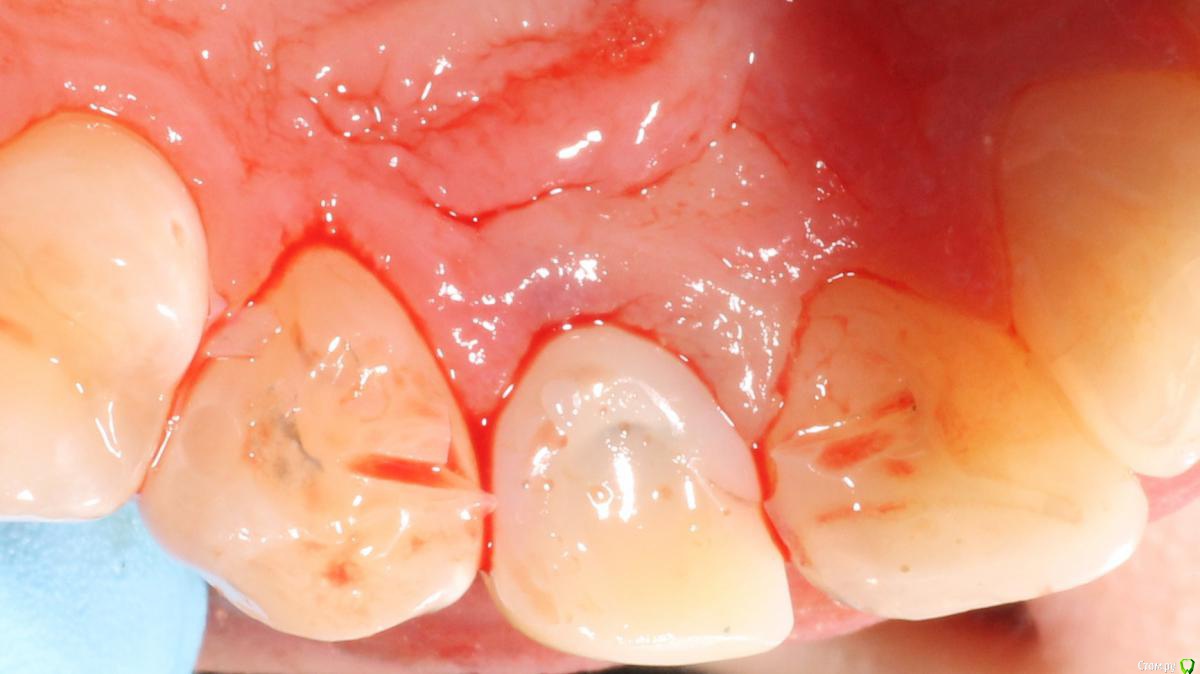

Brigita Опубликовано 5 апреля, 2015 Поделиться Опубликовано 5 апреля, 2015 на удаленном зубе какая то железячка хвостиком торчит))) Ссылка на комментарий

Saymon Опубликовано 6 апреля, 2015 Поделиться Опубликовано 6 апреля, 2015 на удаленном зубе какая то железячка хвостиком торчит)))Все нормально. Это WI-FI антенна. 4 Ссылка на комментарий

MenshikovDV Опубликовано 7 апреля, 2015 Автор Поделиться Опубликовано 7 апреля, 2015 ИНСТРУМЕНТ сломан в канале )) Ссылка на комментарий